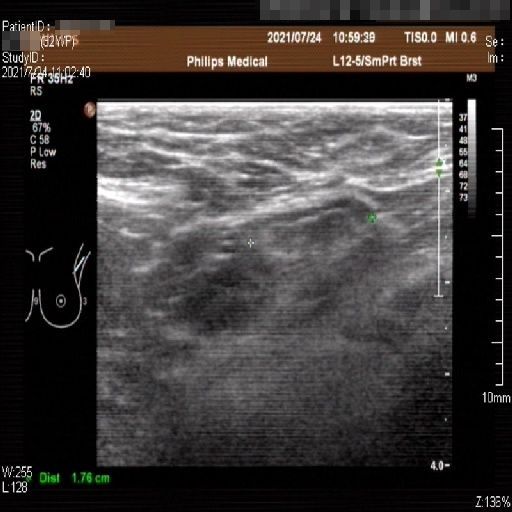

Images with certain annotations are considered noisy images in the context of the noise removal task, and corresponding images without these annotations are considered clean. Some typical images with various annotation are provided in Fig. 1.

In essence, a body marker annotation is a marker selected from a fixed set of icons that indicates different regions of the human body and its current orientation. It is typically located at the edge of the ultrasnoic image area and is labeled by the sonographer. On some ultrasound machines, the body marker annotation has a fixed position.

Refer to caption

Figure 1: Images with various annotations. (a) body marker annotation, (b) radical line annotation, (c) vascular flow annotation.